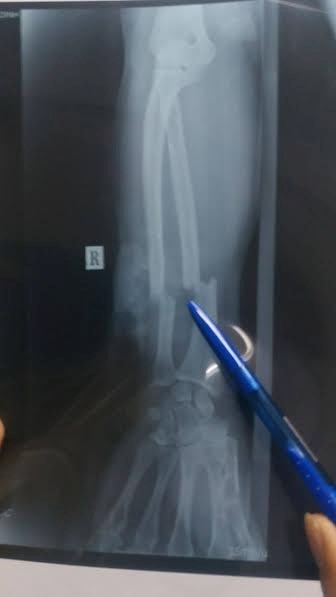

23/10/2016 01:37Nối thành công cánh tay người đàn ông bị chém đứt lìa

Người đàn ông đang chạy xe máy thì bất ngờ có hai người từ phía sau trờ tới vung đao chém đứt lìa cánh tay, các bác sĩ bệnh viện Gia Định mất 6 tiếng đồng hồ để phẫu thuật nối lại cánh tay của nạn nhân.

Theo đó, cánh tay của nạn nhân bị chém đứt lìa xương cẳng tay phải, cánh tay và cẳng tay chỉ còn dính với nhau bằng một phần thịt mềm rất nhỏ; bó mạch máu, thần kinh cẳng tay bị đứt phải thực hiện vi phẫu.

| Cánh tay nạn nhân bị chém đứa lìa xương. |

Trước đó, chiều 21/10, ông Bình đang chạy xe máy trên đường Đinh Tiên Hoàng, quận Bình Thạnh theo hướng về chợ Bà Chiểu. Khi vừa qua cầu Bông, phường 1, quận Bình Thạnh thì bị hai người lạ mặt từ phía sau lao lên chém vào cánh rồi rồ ga bỏ chạy.

Người dân gần đó nhanh chóng đưa nạn nhân đi bệnh viện cấp cứu. Hiện công an đang tiếp tục điều tra vụ việc.